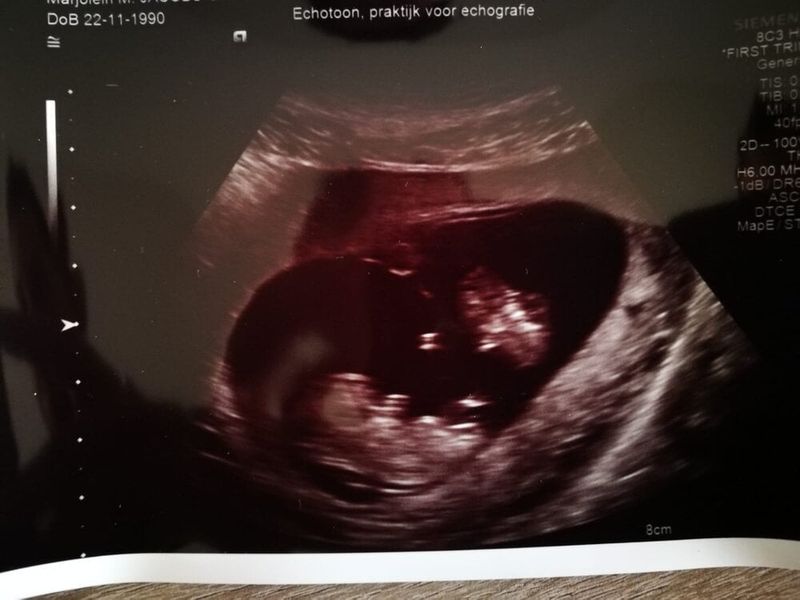

In mijn hoofd ga ik weer toe naar dat moment. De nacht van 23 op 24 februari 2019. Ik lig in het LUMC opgenomen en mijn man ligt naast mij. Mijn twee kindjes worden meermaals per dag gemonitord, maar niet in de nacht. Ik heb al zóveel meegemaakt in deze zwangerschap. TTS, operatie, tussenvlies gescheurd, vochtverlies, veel harde buiken, vermoeden van infectie, en nu lig ik hier, wachtend op wanneer de meisjes gehaald worden omdat één van de twee het moeilijk krijgt. Sinds het tussenvlies kapot was gegaan tijdens de operatie heb ik al een onbestemd gevoel. Zo’n gevoel wat je heel ver weg probeert te drukken en wat je omgeving al helemaal het liefst in de kiem wil smoren. Omdat je vooral positief moet blijven en het allemaal wel goed komt. En toch zit het er. Dat kleine stemmetje wat zegt: ”Doe nog maar even rustig aan met die tweelingbox..” Zo’n naar gevoel, omdat je gewoon twee levende kindjes in je draagt, die bewegen, die het goed doen en die beiden gezond zijn, ondanks dat het zo’n risicovolle zwangerschap is.